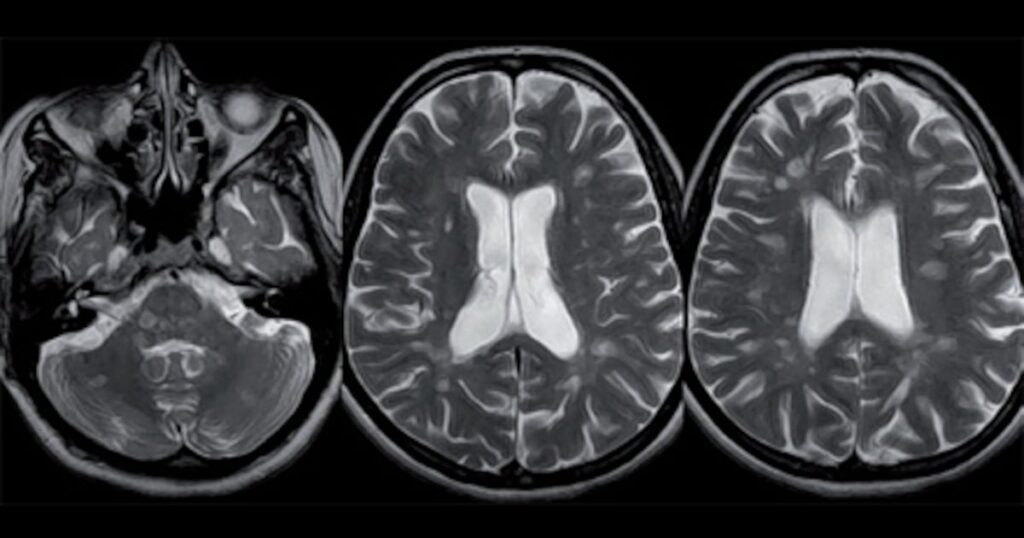

Spécialiste des maladies neurodégénératives, Axoltis Pharma va pouvoir faire progresser le développement de son unique candidat-médicament, le NX210c. Basée à Clermont-Ferrand, la biotech a ainsi levé 18 millions d’euros lors d’un tour de table de série A, composé d’une augmentation de capital et d’un financement participatif.